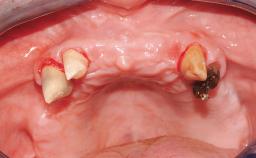

Immediate Loading of Eight Implants in the Maxilla and Six Implants in the Mandible and Final Restoration with Three-Unit and Four-Unit FDPs

Extensive scientific evidence has confirmed that immediately loaded implants with fixed full-arch provisional restorations can osseointegrate with success rates similar to conventionally or delayed loaded implants. A number of immediate-provisionalization techniques for edentulous jaws have been described. Some protocols differ when it comes to prefabricated provisional templates versus complete denture conversion; intrasurgical impressions versus direct relining; and cemented versus screw-retained provisional restorations. In this context, complete-denture conversion has been proposed for either intrasurgical impressions or direct relining. Another possibility is the utilization of a prefabricated provisional to be adapted either in the mouth (by direct relining) or in the laboratory (on a working model obtained from an intrasurgical impression).

Case Type Edentulous Maxilla

Defining Characteristics Fully edentulous upper jaw to be rehabilitated with four or more implants

Defining Characteristics Fully edentulous upper jaw to be rehabilitated with an implant-borne fixed dental prosthesis

Soft Tissue Contour and Volume Slightly compromised